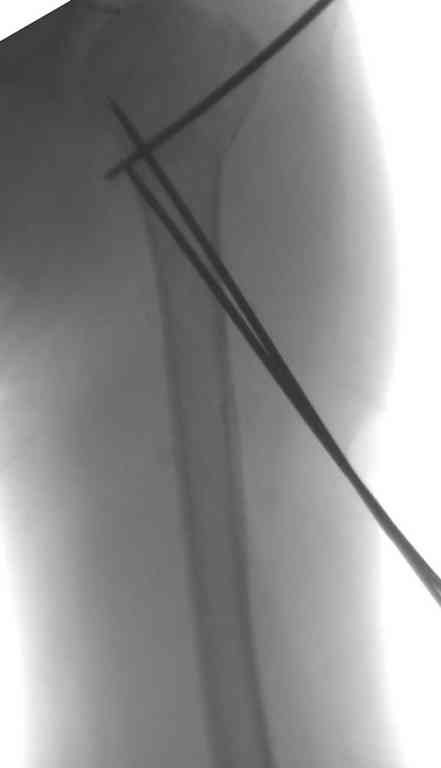

Сделали напряженными спицами по методике А.Ф.Лазарева со товарищи Репозиция сделана спицевым дистрактором, проксимальная спица была проведена в полскости деформации перпендикулярно оси наклонившейся головки. Получилось все довольно легко. Спицы малость покороче можно было сделать, ну да удалять потом легче будет.

Картинка в приложении.

В приложении. Схема простая - по спице в каждый отломок, полукольцо проксимально, кольцо дистально, два телескопа. Как уже писал, ключевым моментом было введение спицы в плоскости диформации проксимального

оттдела плеча.